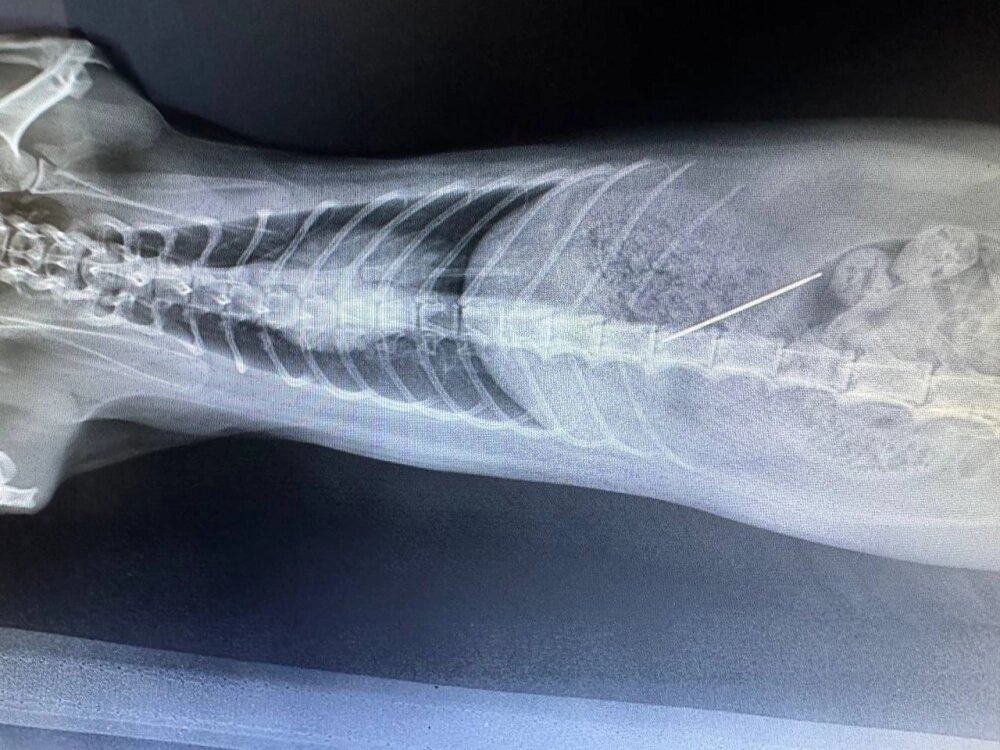

В государственной ветклинике Севастополя провели экстренную операцию двухлетней кошке Миле, которая проглотила иглу с ниткой. Об этом в своем Telegram-канале сообщил губернатор города Михаил Развожаев.

Хозяева срочно обратились в клинику. Рентген подтвердил, что игла находится в желудке животного – требовалось немедленное вмешательство.

Фото: Правительство Севастополя/ Губернатор Севастополя Михаил Развожаев.

Ветеринар Александра Полиновская успешно провела операцию и извлекла инородный предмет. Кошке назначили курс антибиотиков для профилактики осложнений и восстановления.